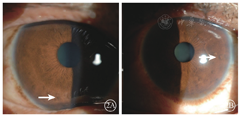

患者女,51岁,因左眼视力下降6年于2018年1月15日到吉林大学第二医院眼科就诊。否认相关既往史及家族史。患者颜面部及上肢可见多个神经纤维瘤及咖啡斑(图1)。眼科检查:右眼、左眼矫正视力分别为1.0、0.15。双眼虹膜见Lisch结节(图2),其余眼前节正常。眼底彩色照相、FAF及FFA检查,双眼均未见异常。红外眼底成像检查,双眼后极部多发片状强反射病灶(图3)。OCT增强深度成像(EDI-OCT)检查,与红外眼底成像强反射病灶对应处脉络膜毛细血管层反射增强(图4)。ICGA检查,早期可见与红外眼底成像强反射病灶相对应处呈弱荧光,随着时间延长,中晚期弱荧光面积逐渐缩小直至消失(图5)。诊断:Ⅰ型神经纤维瘤病。

Ⅰ型神经纤维瘤病是一种常见的常染色体显性遗传病,高达50%的患者是自发突变的结果,患者可以在任何系统中发生良性或者恶性肿瘤,体表可见多发的神经纤维瘤以及牛奶咖啡斑[1]。1988年美国国立卫生研究院制定的神经纤维瘤病的诊断标准指出,在多发性皮肤咖啡斑、神经纤维瘤、腋窝或腹股沟区雀斑、视神经胶质瘤、Lisch结节、特征性骨病变、家族史中存在任何两项即可诊断为Ⅰ型神经纤维瘤病[2]。本文报道的两例患者均具有多发咖啡斑、神经纤维瘤、Lisch结节及家族史,Ⅰ型神经纤维瘤病诊断明确。Lisch结节由增生的黑色素细胞组成,紫外线可以促进其增生,随着年龄的增加,虹膜接受更多的紫外线照射,Lisch结节的数量随之增加[3]。而在Lisch结节的位置分布上,接受紫外线照射较多的下半部虹膜多于接受紫外线照射相对较少的上半部虹膜[4]。与文献报道相符,例1患者较例2患者年长25岁,可见其双眼虹膜Lisch结节数量及体积显著大于例2患者,且大多分布于下方虹膜。